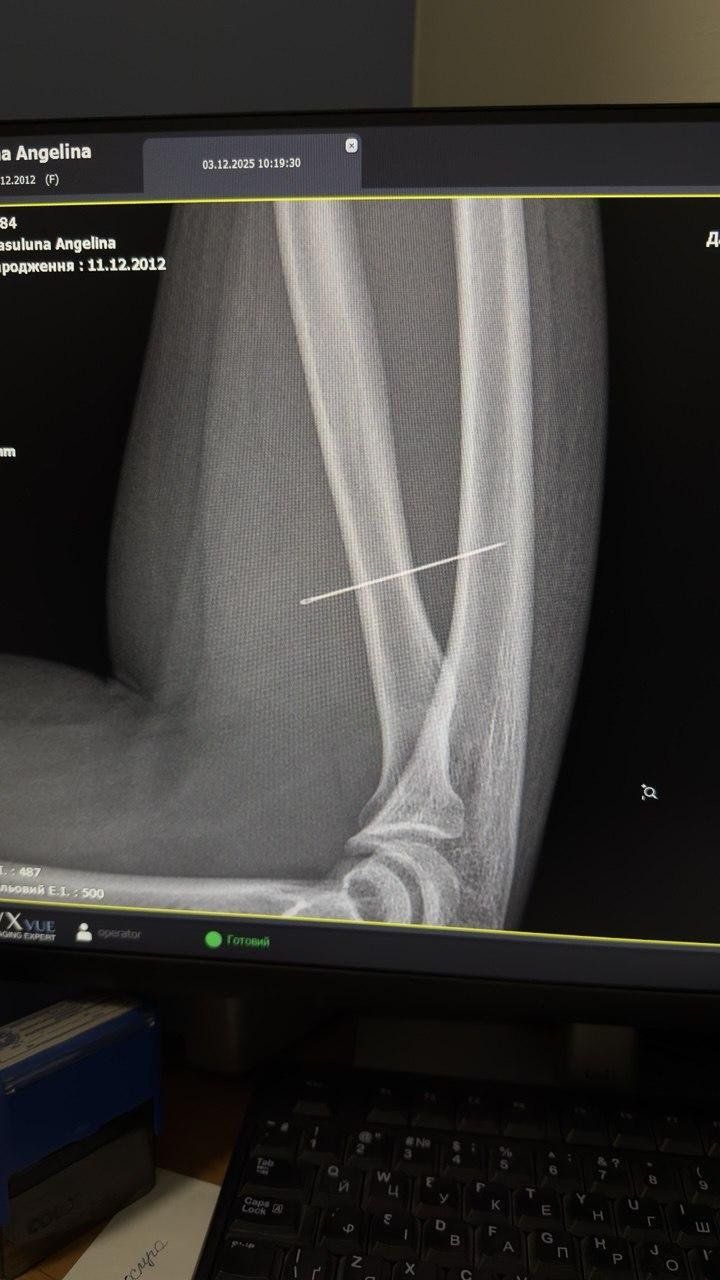

Тиждень школярка проходила з голкою в руці, тому вона просунулася глибше. Вже на рентгені лікарі виявили, що предмет був під кутом 45 градусів і застряг глибоко в товщі м’яза. Якби голка пішла ще далі, то могла б пошкодити або судини, або нервові закінчення.

Під час операцїі була важлива траєкторія виходу предмету, оскільки у разі поламки пошук дрібних уламків у м’язах є значно важчим завданням. За допомогою рентген-навігації ЕОП хірурги точно визначили місце знаходження стороннього тіла та через невеликий розріз правильно і безпечно його вилучили.